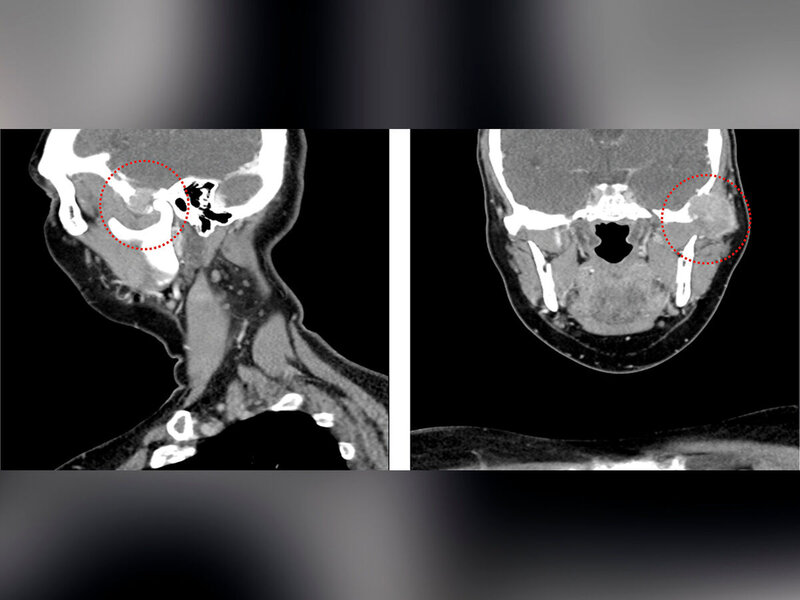

In der durchgeführten CT-Untersuchung mit Kontrastmittel (Abbildung 1) zeigte sich in der linken Gelenkpfanne des Kiefergelenks ein unscharf und destruierend wachsender Tumor mit einem maximalen Durchmesser von etwa 3 cm. Der Tumor arrodierte das Felsenbein und einzelne Mastoidzellen. Die knöcherne Begrenzung der mittleren Schädelgrube zeigte sich nach intrakraniell aufgehoben und die Dura mater zum angrenzenden Temporallappen wurde bereits nach medial verdrängt. Der linke Jochbogen zeigte sich ebenfalls knöchern destruiert, das linke Kiefergelenkköpfchen war jedoch intakt. Im MRT zeigten sich neben einer Tumorinvasion des Musculus temporalis auch ipsilateral links intra- und paraparotideale Lymphknoten, die im Seitenvergleich vermehrt imponierten (Größe < 1 cm). Im Level IIb links zeigten sich im Seitenvergleich ebenfalls vermehrt Lymphknoten, allerdings ohne einen konkreten morphologischen Malignitätsverdacht.